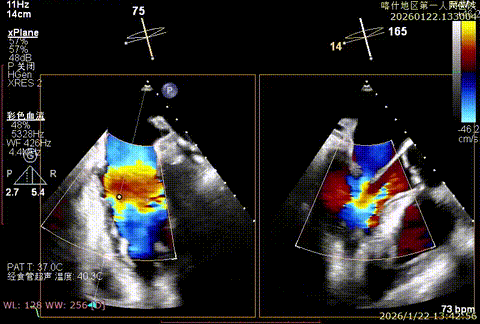

X-plan切面3区后叶脱垂

X-plan切面重度反流

3D enface 观察脱垂

3D enface观察反流